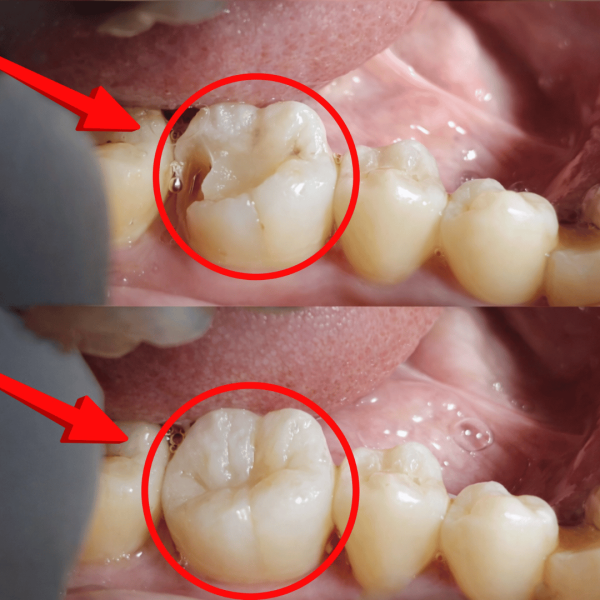

দাঁতের ক্ষয় পূরণ করে ফিরে পান প্রাকৃতিক হাসি! টেক ডেন্টালে উন্নত মানের কম্পোজিট ফিলিং খরচ এখন সাধ্যের মধ্যে। অভিজ্ঞ ডাক্তার ও আধুনিক প্রযুক্তির সেবা নিন আজই।

দাঁতের ক্যাভিটি বা ক্ষয়জনিত সমস্যা আমাদের প্রতিদিনের খাবারে অস্বস্তি এবং হাসিতে জড়তা তৈরি করে। অনেকেই ব্যথার ভয়ে, দাঁত কৃত্রিম দেখাবে ভেবে কিংবা অতিরিক্ত কম্পোজিট ফিলিং খরচ নিয়ে দুশ্চিন্তার কারণে চিকিৎসা নিতে দেরি করেন। টেক ডেন্টালে আমরা আপনার সাধ্যের মধ্যে দাঁতের প্রাকৃতিক গঠন ও রঙ বজায় রেখে আধুনিক ফিলিং নিশ্চিত করি, যাতে আপনি প্রাণ খুলে হাসতে পারেন এবং ব্যথামুক্ত জীবন উপভোগ করতে পারেন।

কম্পোজিট ফিলিং হলো দাঁতের রঙের সাথে মিল রেখে তৈরি এক ধরণের আধুনিক ডেন্টাল রেজিন। এটি দাঁতের ক্ষয়ে যাওয়া অংশ বা গর্ত পূরণ করতে ব্যবহৃত হয়। সাধারণ সিলভার ফিলিংয়ের মতো এটি কালো দেখায় না, বরং দাঁতের সাথে এমনভাবে মিশে যায় যে আলাদা করে চেনা প্রায় অসম্ভব। এটি দাঁতের হারানো শক্তি ফিরিয়ে আনে এবং স্থায়িত্ব বৃদ্ধি করে।

দাঁতের গর্ত বা ক্যাভিটি দূর করার সবচেয়ে আধুনিক ও নান্দনিক সমাধান হলো কম্পোজিট ফিলিং। এটি দেখতে হুবহু প্রাকৃতিক দাঁতের মতো হওয়ায় বর্তমানে এটি সবচেয়ে জনপ্রিয়। অনেকেই উন্নত মানের চিকিৎসার পাশাপাশি বাংলাদেশে কম্পোজিট ফিলিং খরচ কেমন হতে পারে তা নিয়ে চিন্তিত থাকেন। আপনার সেই চিন্তা দূর করতে টেক ডেন্টাল (Tech Dental) দিচ্ছে সাশ্রয়ী মূল্যে প্রিমিয়াম সার্ভিস।